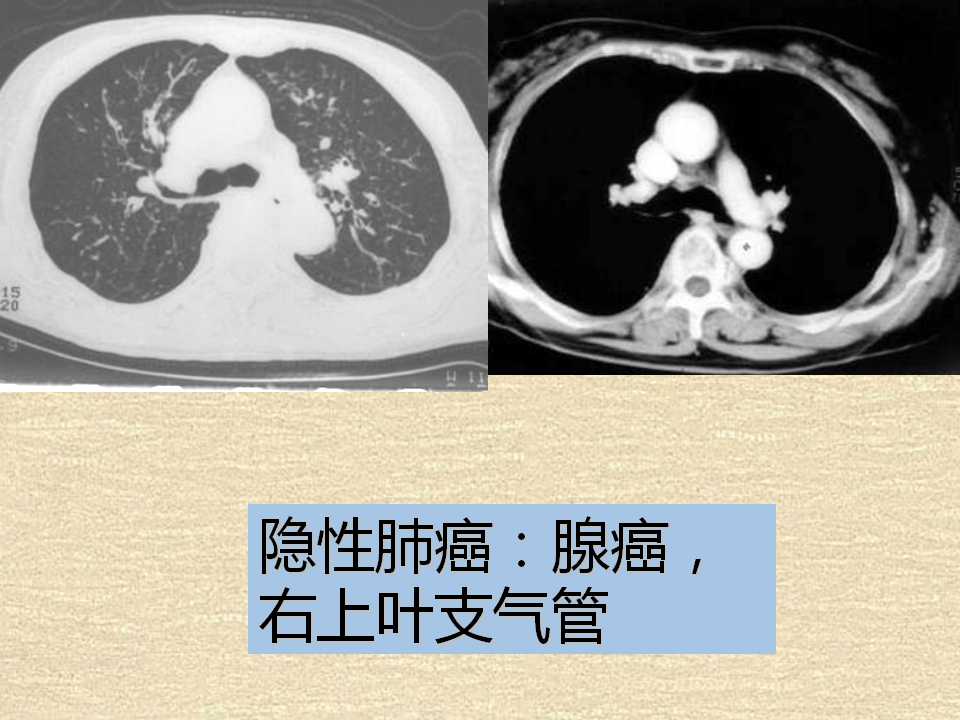

肺癌影像学表现